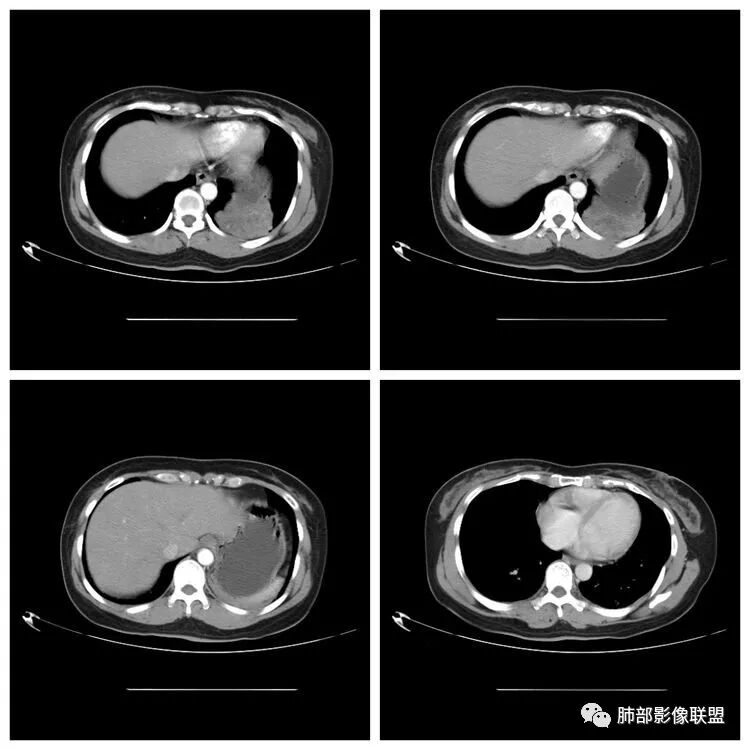

下面看第三部分了,3月20日补增强扫描:

M-Imaging :错了,这么大,膈肌后方南边:定位?定性?Shelia:肺外。感觉病灶是个扁平状,虽然没有蛇纹血管征,但是延迟强化,怀疑纤维来源,考虑sft

M-Imaging :肿块与胸膜夹角是锐角,有分叶,觉得肺内Lotus:mpr重建再看一下南边:与支气管有关系吗Shelia:没有关系。与胸膜分不清

南边:边缘这么光滑,无分叶,与胸膜关系密切

D字征

首先良性,倾向于SFT,不除外PSP

宇宙星空:延迟明显强化,其内可见条索状低密度,支持SFT

lmg:其内可见血管穿行吧,考虑SFT

一米阳光:与膈胸膜关系密切,肺受压。考虑SFT

CT表现:1.多为来自胸膜单发肿块,轮廓较光滑,一般无分叶,可有包膜,可以有胸膜尾征。少数胸膜SFT可表现为带蒂肿块,为本病较为特征性表现。2.当肿瘤较小(小于5cm)时,平扫密度较均匀,为软组织密度,增强扫描呈轻中度均匀强化,少数肿瘤强化较明显。3.随着肿瘤的增大,发生粘液变性、囊变坏死概率增加,多表现为密度不均匀,并可有钙化,增强为轻中度不均匀强化,常表现为“地图样”。

潘军平老师关于定位点评——我们判断肺内肺外的依据:1、与胸膜的关系。主体在外面,宽基底与胸膜连接,胸膜掀起一般是肺外的依据。2.、与肺内结构的关系:附近血管、支气管被推移,未进入病灶(无血供的良性病变有时候要警惕除外),提示肺外。3、血供,肺部来源的一般肺部血供(隔离症除外,恶性肿瘤有时候会有差异,孤立性纤维瘤血供可以肺内来源)。